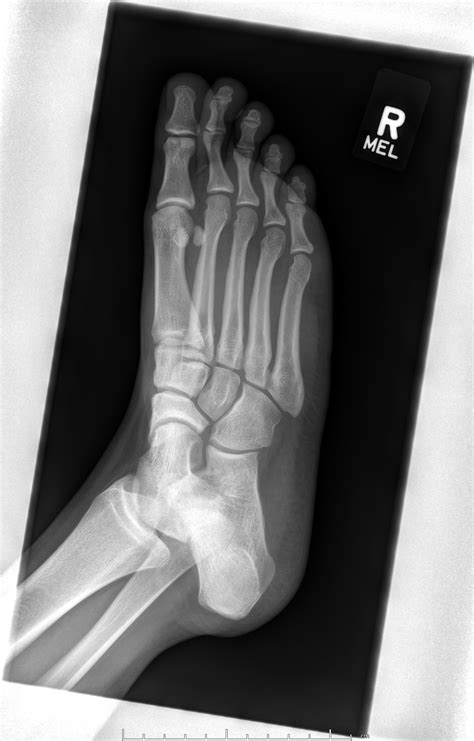

X-ray Imaging Primary scan to identify major breaks or displacement.

MRI or CT Scan Used for occult fractures that are hidden on standard X-rays.